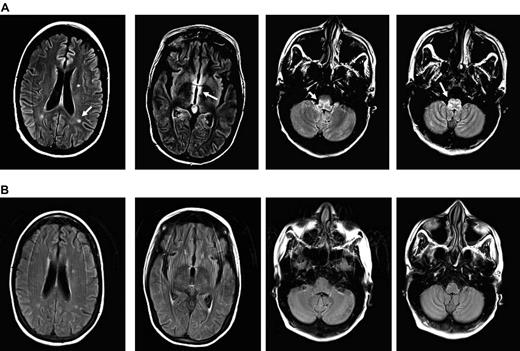

MRI images of CMV encephalitis before and after U-DLI. (A) Axial T2 fluid-attenuated inversion recovery (FLAIR) images demonstrate 3 new white matter lesions, increased signal, and edema in the periventricular region most notable around the third ventricle and medulla (white arrows). (B) Axial FLAIR images demonstrate resolution of previously described lesions and increased signal/edema 6 months after the initial U-DLI.

The patient's neurologic status and T-cell counts remained unchanged despite a decline in CMV copy number after the initial U-DLI, which was given on day +112 (Figure 2). She was 100% donor T-cell chimera before DLI. Following the third U-DLI, she developed localized chronic skin and ocular GVHD, which responded to topical treatments. This was associated with temporary increase in peripheral blood CD4/CD8 counts. After the fourth U-DLI, given at higher doses, her CD4/CD8 counts further increased and remained high afterward. This was clearly associated with decrease in her CMV viral load by PCR (Figure 2) and CMV antigenemia. No steroid therapy was given during any of the DLIs. Antiviral therapy was discontinued because of lack of clinical efficacy. Her neurologic recovery, however, lagged behind viral clearance following U-DLIs. She developed biopsy-proven grade 2 skin GVHD after the last (fifth) high-dose DLI, which responded to a short course of a systemic steroid. Most recently, her CMV was undetectable or positive at very low titer with relatively high peripheral T-cell counts. Her neurologic condition improved in parallel with resolution of MRI lesions (Figure 1B). A follow-up CSF sample examination on day +357 was negative for CMV by PCR.